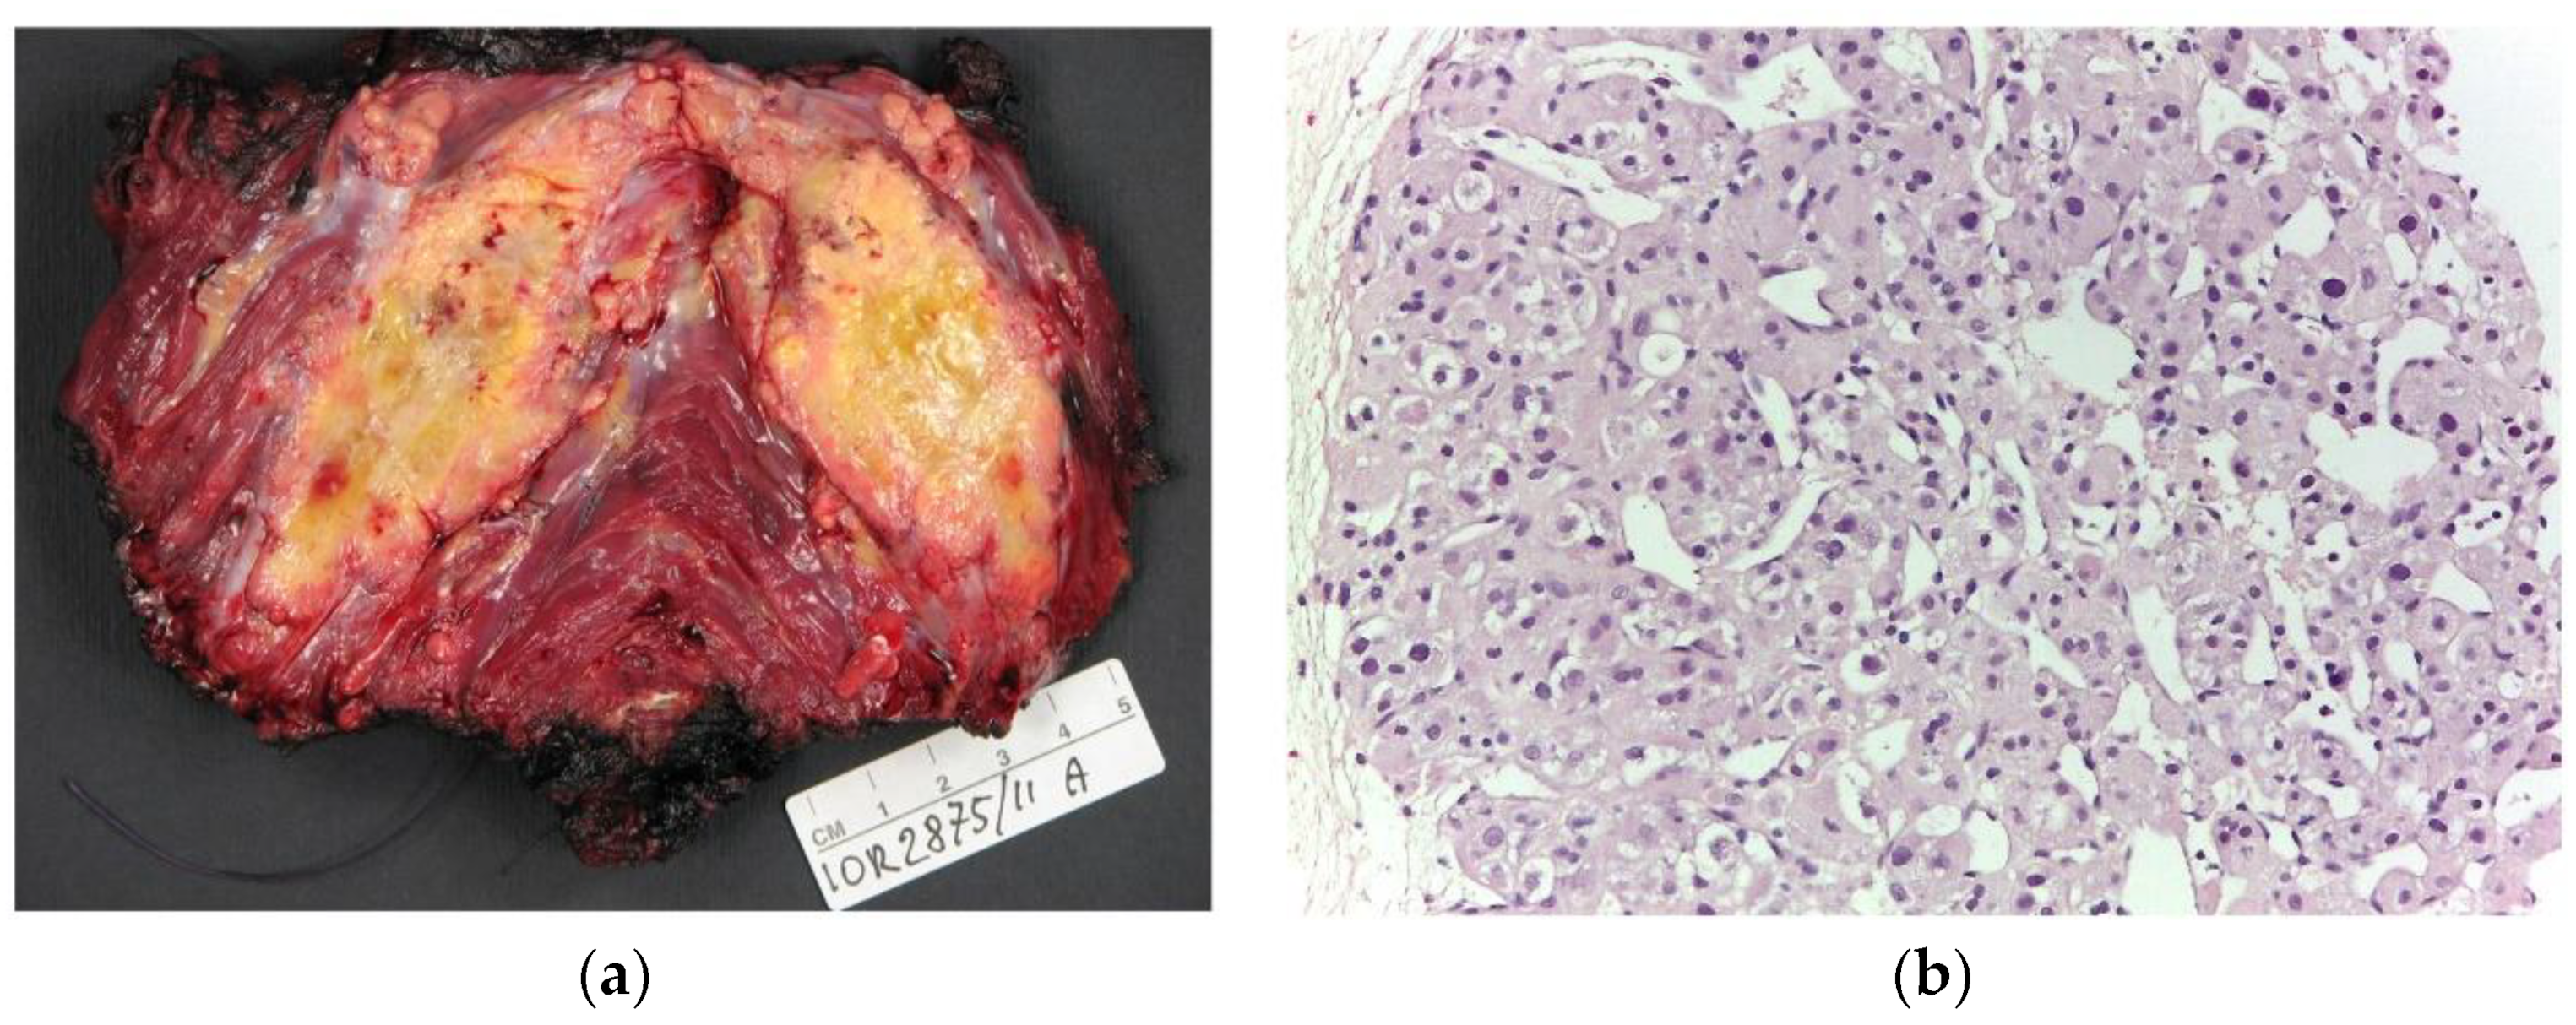

3.2. General Imaging Findings—Local and Distant Baseline Assessment

4. Discussion